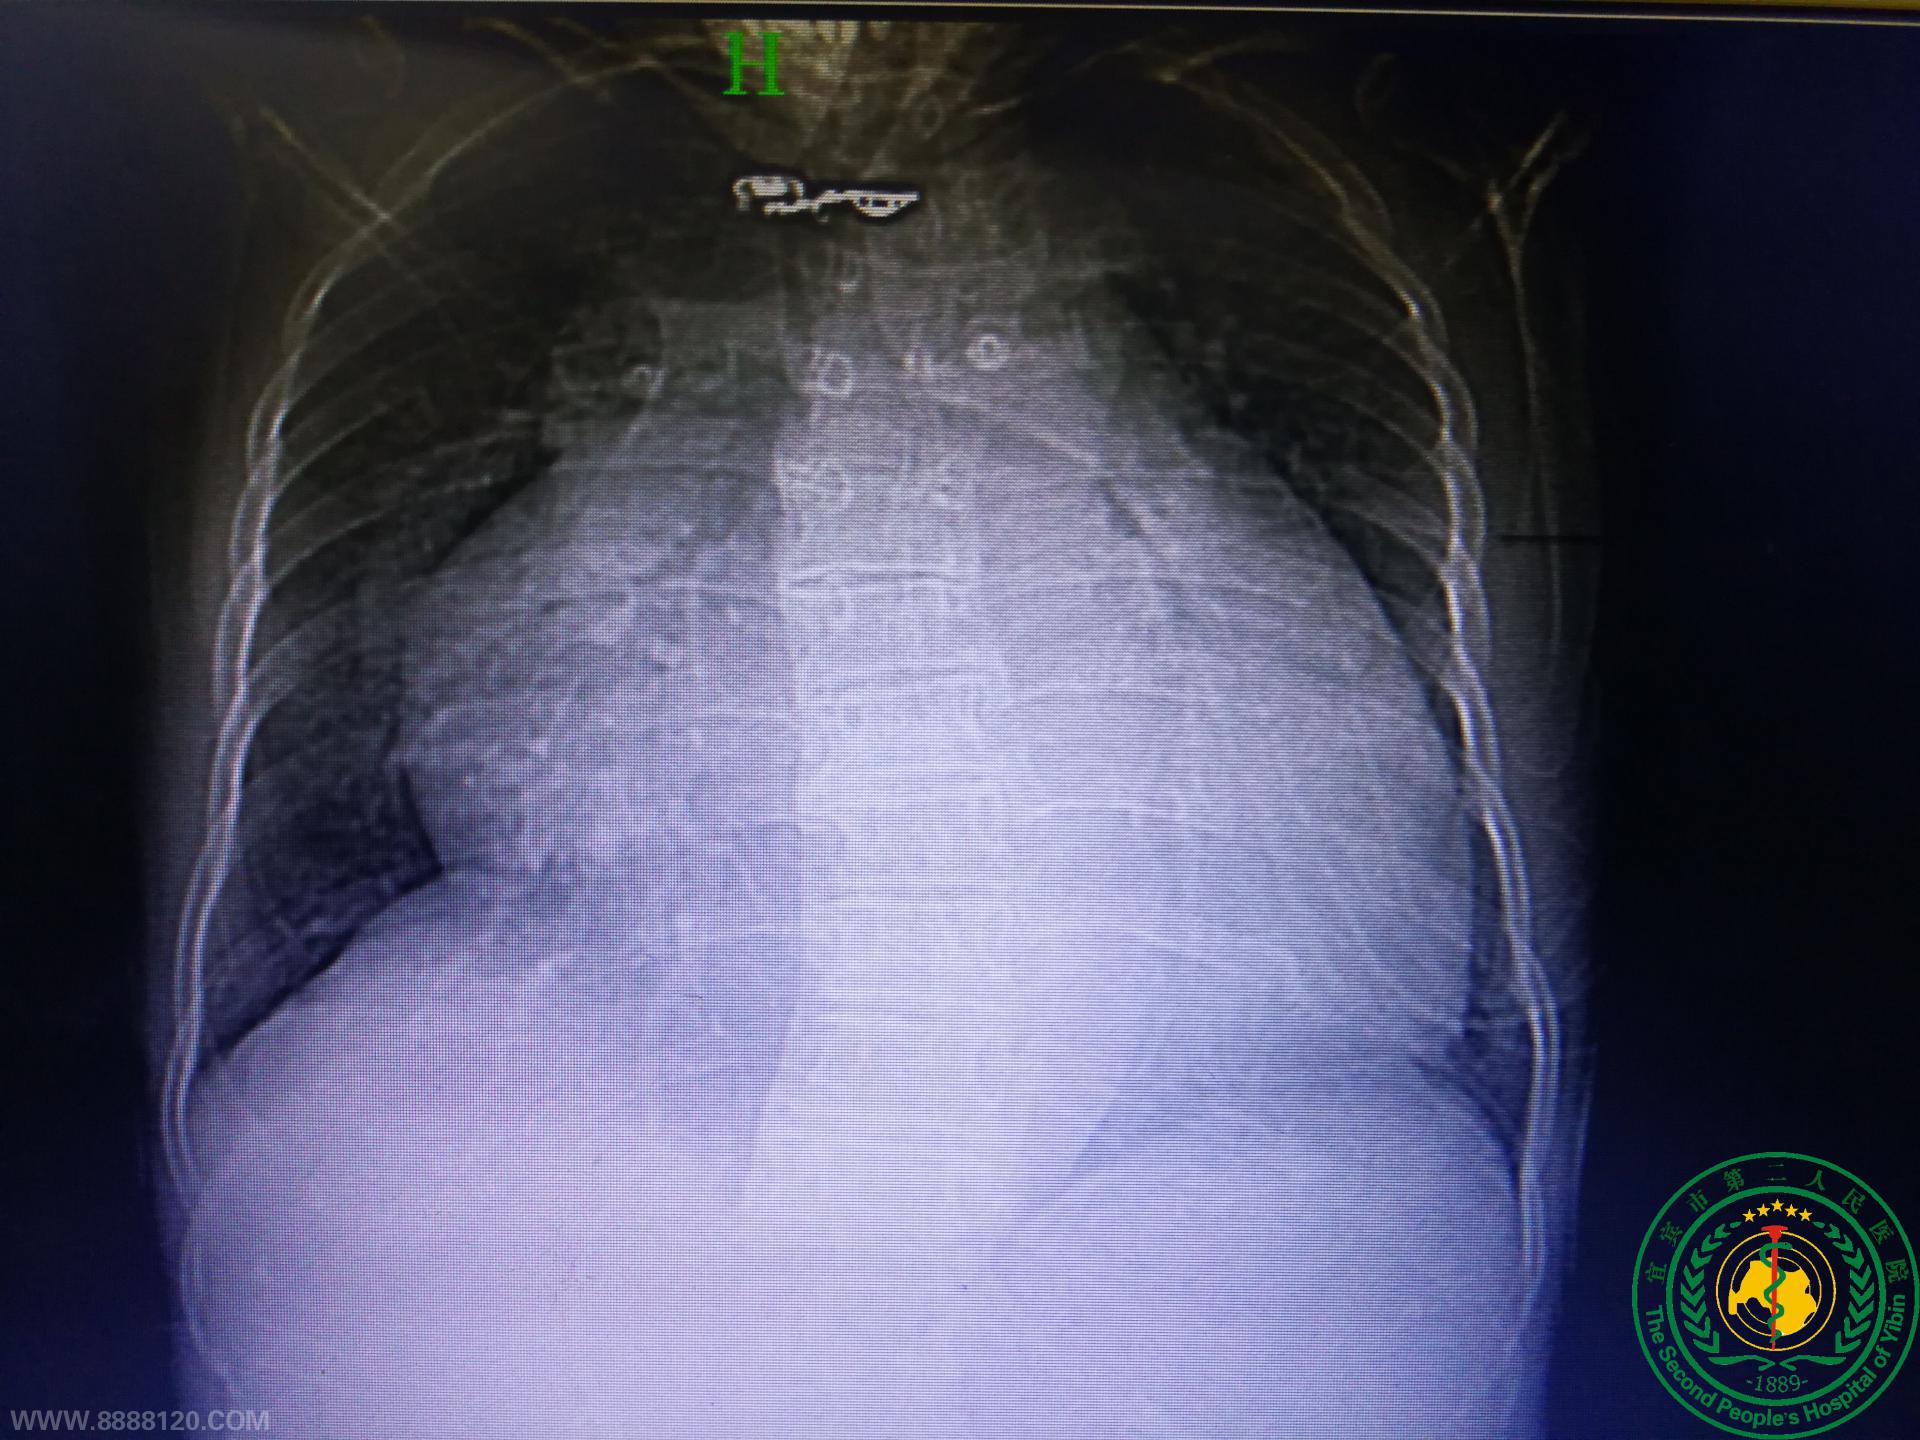

胸心外科完成宜宾首例巨大心脏复杂冠状动脉静脉瘘手术

胸心外科完成宜宾首例巨大心脏复杂冠状动脉静脉瘘手术28242